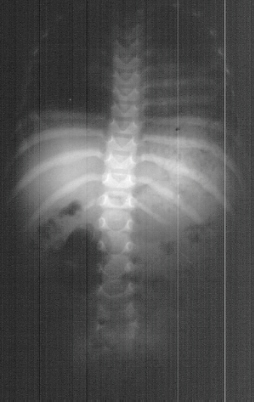

three there was concern about her spine. Radiographic evaluation at age

of 3 (image 1) and age of 6 (image 2)were done.